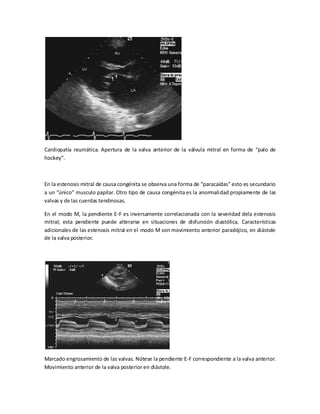

Cardiopatía reumática. Apertura de la valva anterior de la válvula mitral en forma de “palo de

hockey”.

En la estenosis mitral de causa congénita se observa una forma de “paracaídas” esto es secundario

a un “único” musculo papilar. Otro tipo de causa congénita es la anormali dad propiamente de las

valvas y de las cuerdas tendinosas.

En el modo M, la pendiente E-F es inversamente correlacionada con la severidad dela estenosis

mitral; esta pendiente puede alterarse en situaciones de disfunción diastólica. Características

adicionales de las estenosis mitral en el modo M son movimiento anterior paradójico, en diástole

de la valva posterior.

Marcado engrosamiento de las valvas. Nótese la pendiente E-F correspondiente a la valva anterior.

Movimiento anterior de la valva posterior en diástole.